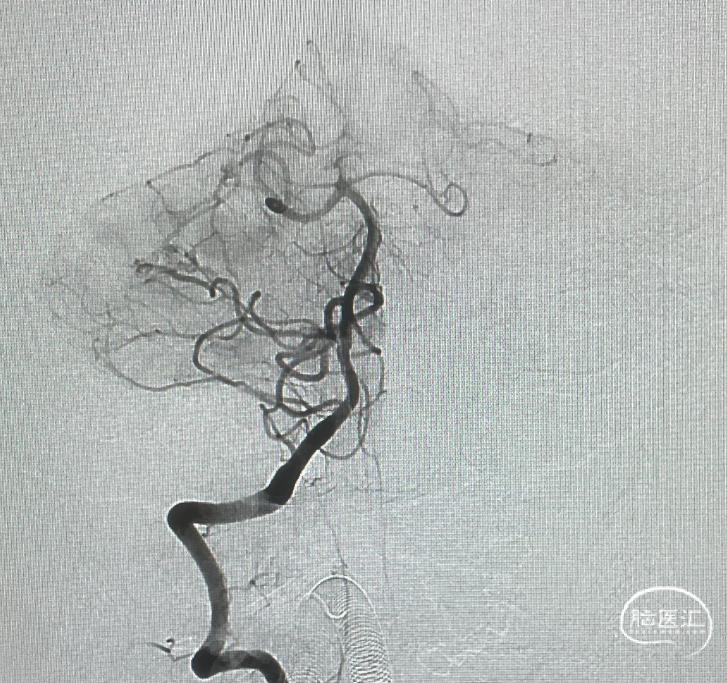

术前造影

证实为TDAVF,为岩上窦型。R-ECA正侧位见右侧脑膜中动脉分支、枕动脉分支、颞浅动脉分支向瘘口供血,经幕上迂曲扩张的静脉、中脑周围静脉、基底静脉向深部静脉引流。

R-ICA正侧位见右侧脑膜垂体干向瘘口供血

L-ICA正侧位见左侧脑膜垂体干分支向瘘口供血

L-ECA正侧位未见向瘘口供血

L-VA、R-VA正侧位右侧小脑上动脉脑膜支向瘘口供血

结构分析:右侧天幕区硬脑膜动静脉瘘,瘘口位于右侧岩上窦,供血动脉主要包括右侧脑膜中动脉的颞支、岩鳞支,右侧枕动脉分支,右侧颞浅动脉分支,双侧脑膜垂体干,右侧小脑上动脉脑膜支,经幕上迂曲扩张的静脉、中脑周围静脉、基底静脉向深部静脉引流,引流静脉起始部见扩张的静脉球。Cognard分型IV型,Borden分型III型,Lawton分型IV型(岩上窦型)。